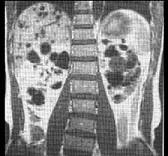

问题 关于囊性肾病变,以下哪几项说法是正确的 ( )

选项 A、多囊肾有家族遗传史 B、单纯性肾囊肿一般无临床症状 C、常染色体显性多囊肾的特点是于成年时出现症状 D、常染色体隐性多囊肾未成年时就已出现症状 E、单纯性肾囊肿绝大多数为非遗传性疾病

答案 ABCDE